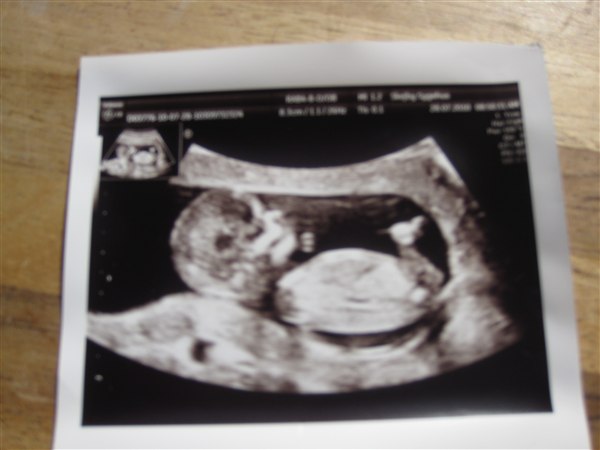

Jeg glæder mig til at gå på barsel d. 18/10 - først dér tror jeg jeg kan begynde at forholde mig til et nyt barn for alvor - og så skal der nok fart over feltet med at omrokere det lille hjem, så kontoret bliver til pigeværelse, hente tøj hjem fra diverse låne-steder - jeg har ikke købt et eneste stykke nyt noget som helst endnu - i uge 28 med William tror jeg ALT var klart!! Så ja, fokus ligger helt klart på William - og det tror jeg da er helt naturligt - vi kender jo ikke de små endnu - og de vokser jo uanset om vi følger med i hvad de nu kan derinde.